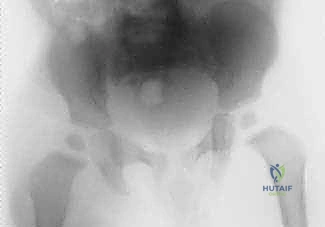

- الأشعة السينية (X-rays): تُجرى لاستبعاد وجود كسور أو أورام. في الأيام الأولى للالتهاب القيحي، قد تظهر الأشعة طبيعية، أو قد تظهر اتساعاً في المسافة المفصلية بسبب تجمع الصديد، أو خلعاً جزئياً لرأس الفخذ. التغيرات العظمية المدمرة لا تظهر إلا في مراحل متأخرة (وهو ما نسعى لتجنبه).